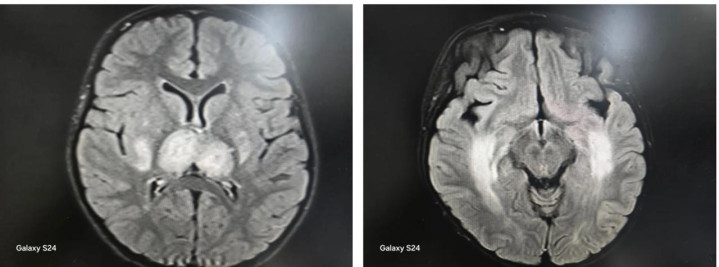

“前几天我们接诊了一名6岁女童,从咳嗽发热到抽搐昏迷,仅仅用了一天时间。”龙梅主任回忆道,孩子送来时已处于昏迷状态,面色苍白,经过紧急检查,最终确诊为“儿童急性坏死性脑病”——一种由流感引发的罕见却极其凶险的中枢神经系统并发症。

急性坏死性脑病主要发生在婴幼儿和儿童群体,多由甲型流感病毒感染诱发。它的可怕之处在于,发病机制并非病毒直接侵袭大脑,而是病毒感染后触发人体过度、失控的免疫反应。

“我们称之为‘炎症风暴’。”龙梅主任用形象的比喻描述,“就像身体的免疫系统突然‘暴动’,原本应该保护机体的免疫细胞开始疯狂攻击自身组织,特别是脑部血管和神经细胞,导致大脑多部位发生对称性坏死。”